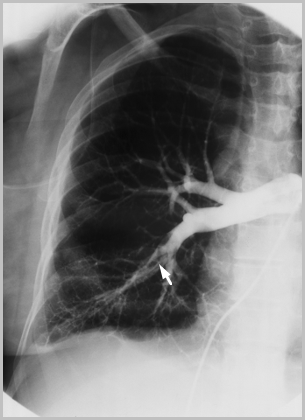

ARTERIOGRAFIA PULMONAR

Defectos intraluminales de llenado